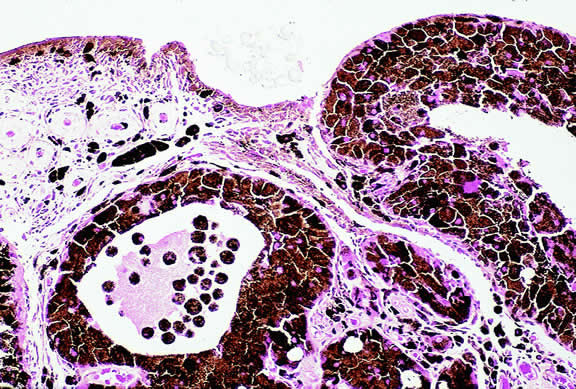

Lymphoma

Although non-Hodgkin's lymphoma often affects the orbit and conjunctiva, intraocular involvement by lymphoma is relatively rare and occurs in two basic ways. First, patients who have widely disseminated systemic lymphoma may develop secondary ocular involvement whose typical manifestation is uveal infiltration. Second, in the variant of central nervous system (CNS) lymphoma that has been called primary lymphoma of the CNS and retina, the vitreous characteristically is involved and the uvea is spared. The latter entity also has been called vitreous large cell lymphoma or ocular “reticulum cell sarcoma.”205–208 In addition to the vitreous, the lymphoma cells also infiltrate the retina, and typically collect between Bruch's membrane and the retinal pigment epithelium, forming solid yellowish RPE detachments, which are highly suggestive of the diagnosis. This rare variant of primary CNS lymphoma should be suspected in older patients who have chronic vitritis that is unresponsive to therapy. Cytologic examination of diagnostic vitrectomy specimens reveals a highly cellular and extensively necrotic infiltrate that contains atypical lymphocytes with prominent nucleoli and protrusions of the nuclear membrane (Fig. 53). The significance of elevated vitreous interleukin 10 levels as a diagnostic marker for lymphoma is controversial.209,210

Fig. 53. Primary central nervous system lymphoma, vitreous. Diagnostic vitrectomy specimen contains large atypical lymphocytes, necrotic lymphoid cells, and nuclear debris. Lymphoma cells in inset have nuclear membrane protrusions and prominent nucleoli. Main figure, Millipore filter. (Hematoxylin-eosin, × 250.)